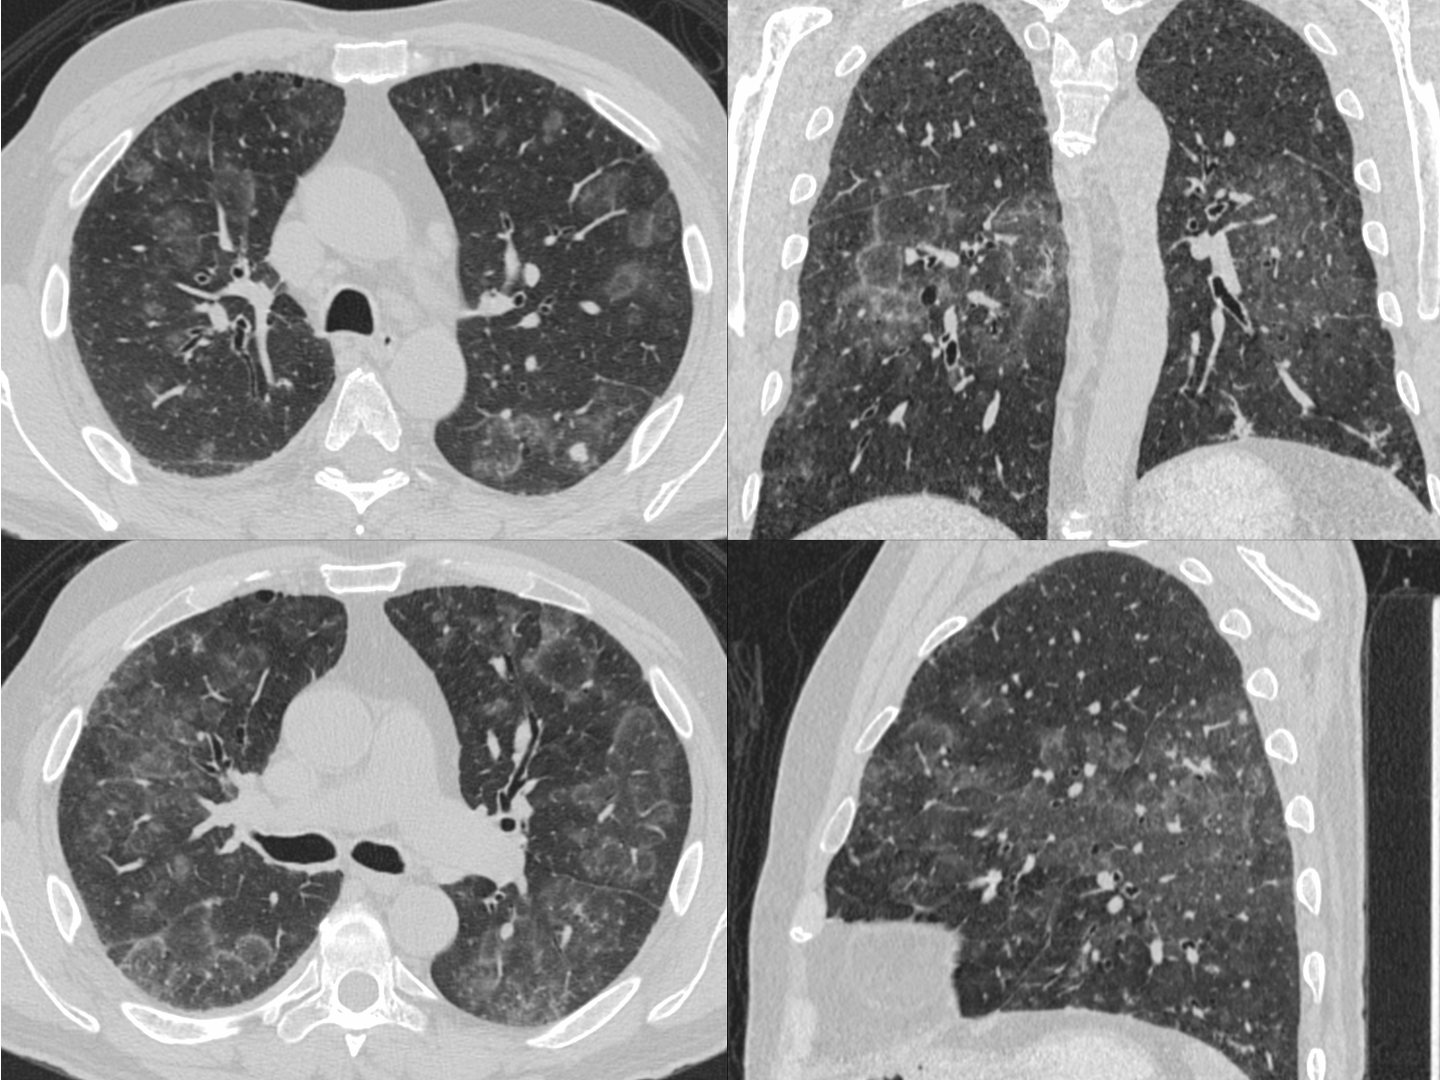

65-years old on pembrolizumab for metastatic renal cell carcinoma has mild breathlessness

The CT scan shows confluent lesions with central lucency and peripheral high density rings.